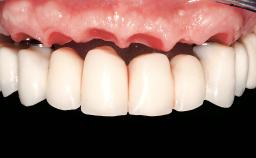

Early Loading of Two Implants in the Mandible and Final Restoration with a Retentive-Anchor-Supported RDP

A 63-year-old male edentulous and maladaptive patient presented with an inability to wear his existing complete maxillary and mandibular dentures. He had been edentulous for 41 years, and there had been three unsuccessful attempts by dentists to provide complete dentures for him. Efforts to wear both complete dentures were always initially encouraging, but over time, he invariably found that he was unable to wear the complete mandibular denture, and this pattern had persisted for 20 years. After seeing local newspaper advertisements, he requested having his complete mandibular denture stabilized with implants.

Prosthesis Type RDP